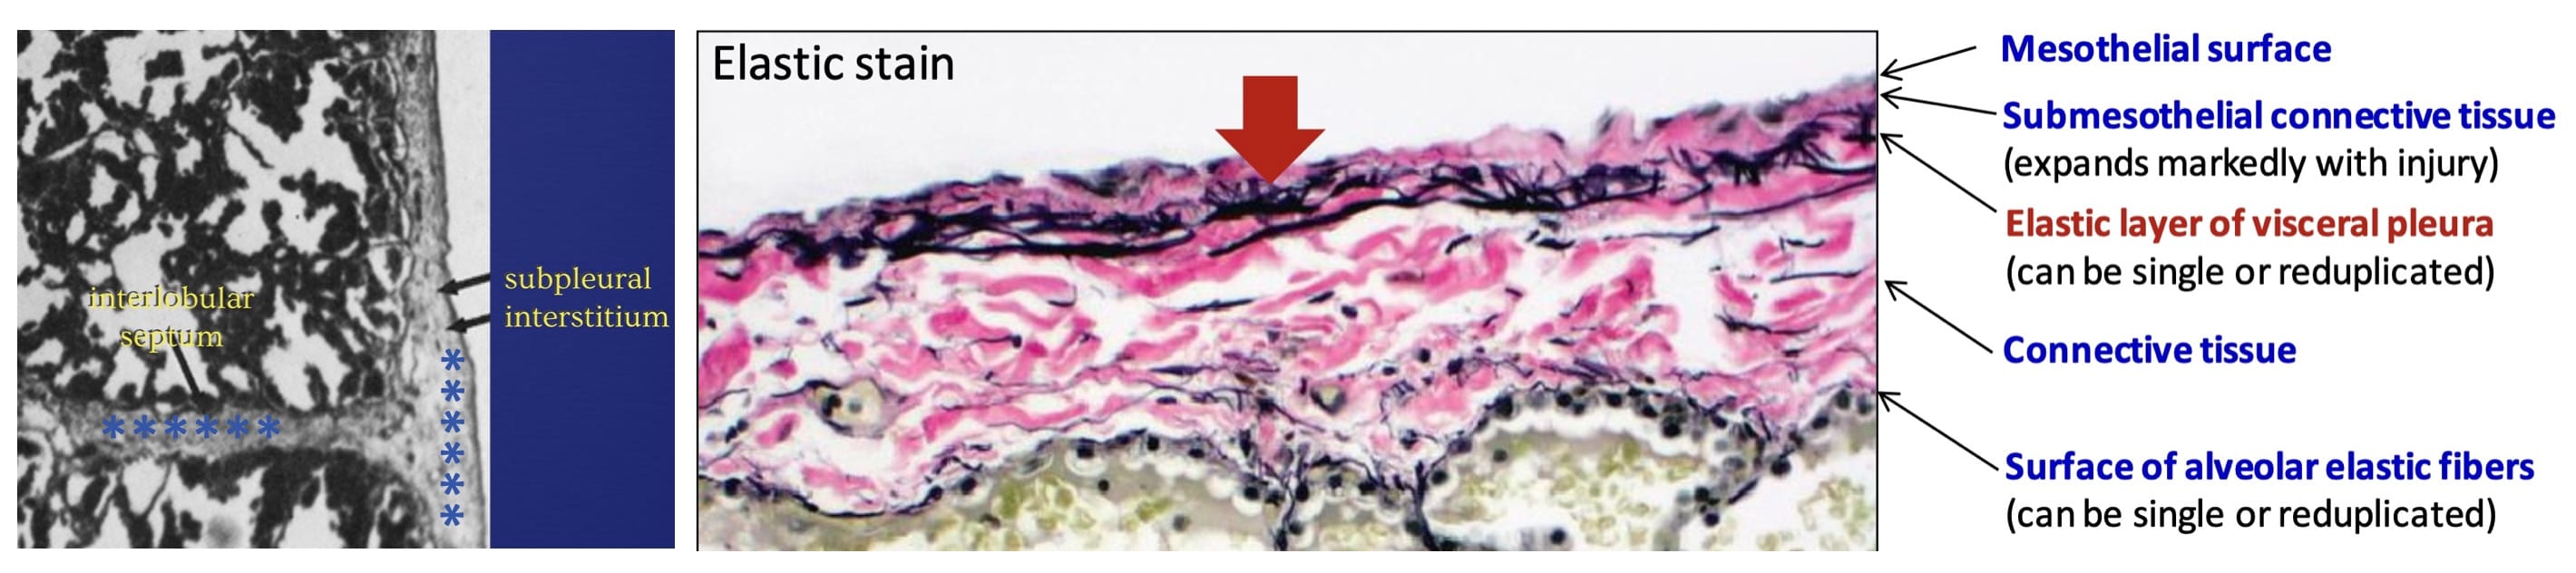

Subpleural interstitial edema

Anatomy of the subpleural interstitium

When two of these sub-visceral pleural compartments are contiguous, as is the case in relation to the interlobar fissures, the accumulating fluid (blue asterisks) suggests “thickening” of the fissures.